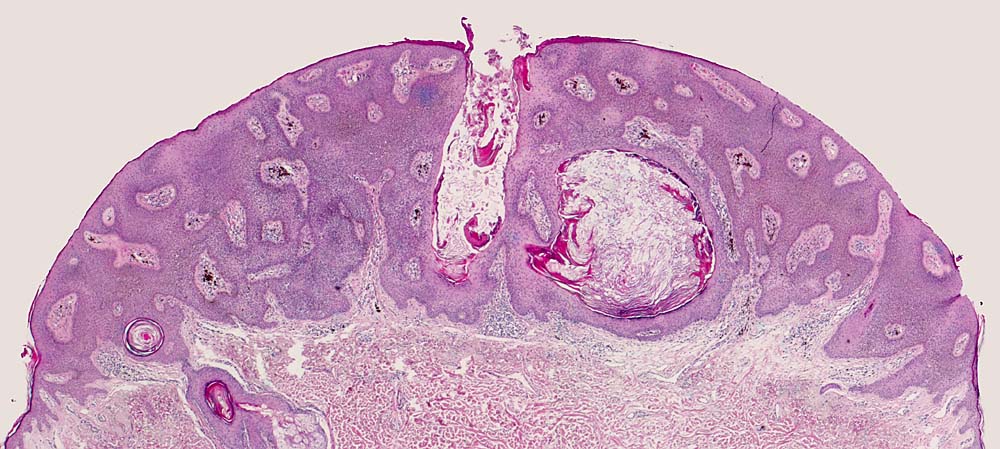

Pigmentierte seborrhoische Keratose vom akanthotischen Typ

Akanthotische seborrhoische Warze mit ausgeprägter Pigmentierung. Melanophagen in der papillären Dermis. Keratingefüllte Epidermisinvagination und Hornzysten.

Hauttumor am Nacken. Melanom?

Histologie

25